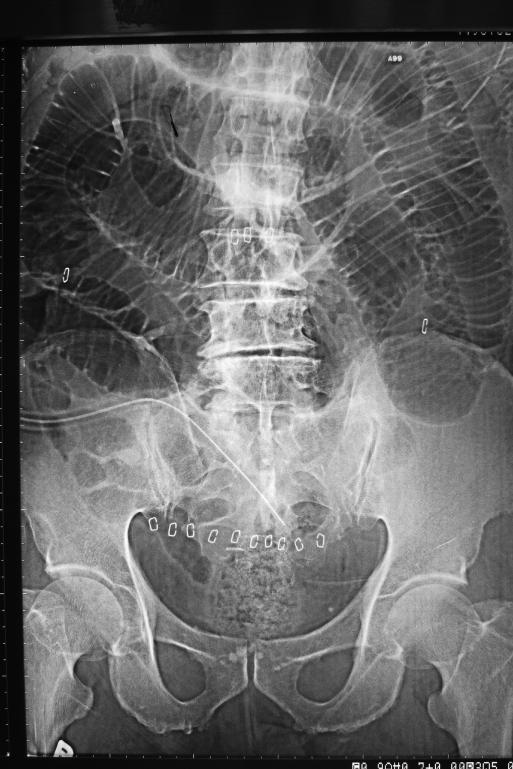

We report a rare drain-related complication leading to small bowel obstruction after laparoscopic colectomy. An 82-year-old man developed small bowel obstruction on the second day after laparoscopic anterior resection. Emergency relaparoscopy found herniation of the small bowel mesentery into the side holes of the silicon intraabdominal drain, which led to a 90-degree acute turn of the small bowel and mechanical obstruction. The herniation was reduced, and the drain was removed laparoscopically.

我们报告了一例腹腔镜结肠切除术后罕见的与引流管相关的并发症,导致小肠梗阻。一名82岁男性在腹腔镜前切除术后第二天出现小肠梗阻。急诊再次腹腔镜检查发现小肠系膜疝入腹腔内硅胶引流管的侧孔,导致小肠呈90度急性扭转并机械性梗阻。将疝内容物还纳,并通过腹腔镜移除了引流管。